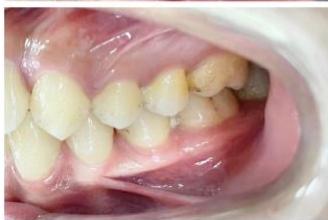

### b) Intraoral Examination

Intraoral examination revealed severe proclination and protrusion of both the maxillary and mandibular incisors [6]. The occlusal relationship was Class I at the canine (tooth 3) and first molar (tooth 6) levels bilaterally. A critical unfavorable biological factor was the proximity of the mandibular incisor roots to the labial cortical plate, representing a high-risk condition when planning extraction-based anterior retraction mechanics [10-12]. All four third molars were present.

Figure 2: Pre-Treatment Intraoral Photographs